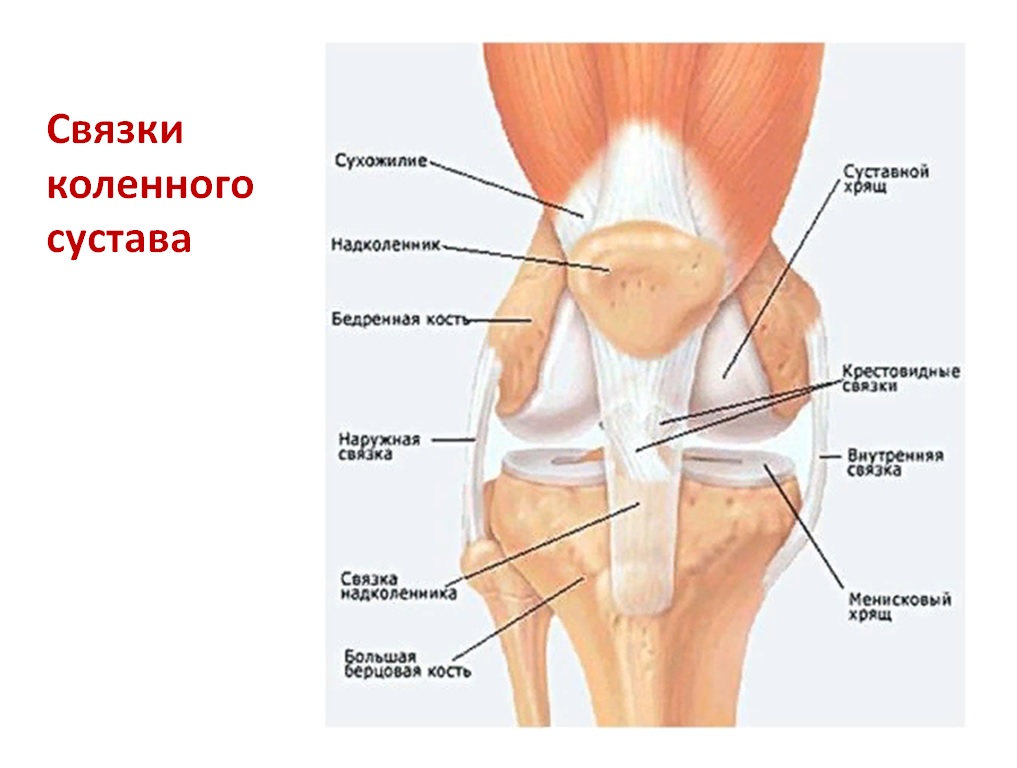

Проблемы с коленным суставом: флоттация и лечение